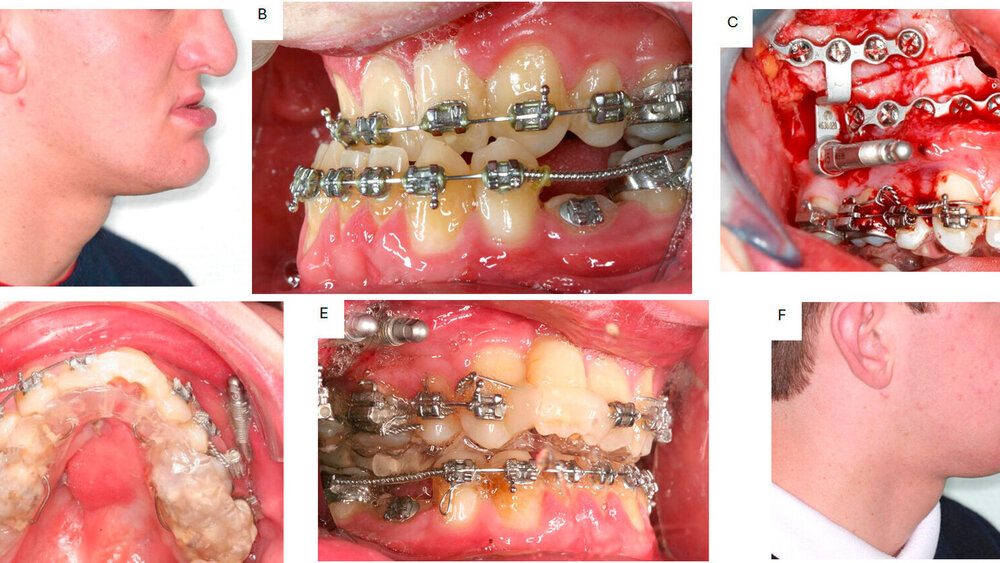

Ein traditionelles Anwendungsgebiet der Unterkieferdistraktion stellt die uni- oder bilaterale Mikrognathie des Unterkiefers bei kraniofazialer Mikrosomie dar (Abbildung 5).

Befürworter der Distraktion argumentieren, dass die in jedem Fall notwendige Umstellungsosteotomie vom vermehrten Knochenangebot der vorangegangenen Distraktion signifikant profitiert, wodurch ein besseres ästhetisches Ergebnis gegenüber der alleinigen bignathen Umstellung erreicht werden kann [Shakir und Bartlett, 2021]. Zu beachten ist die Gefahr einer Kondylusresorption des häufig nur rudimentär ausgebildeten Kiefergelenks als Folge der hohen Druckbelastung bei gleichzeitig insuffizienter Abstützung während einer Ramusdistraktion. Dieses Risiko kann und sollte durch die Eingliederung einer kieferorthopädischen Aufbiss-Apparatur und von anterioren Gummizügen zur Druckentlastung der Gelenkregion verringert werden (Abbildung 6).

Klassisches Anwendungsgebiet der Le-Fort-I-Distraktion sind LKG-Patienten mit sehr hypoplastischem Oberkiefer und damit einhergehender ausgeprägter Klasse-III-Kieferbasenrelation (Abbildung 8). Hier ermöglicht die Distraktion gegenüber der Umstellungsosteotomie aufgrund der graduellen Dehnung der restriktiven Weichgewebe deutlich größere Vorverlagerungen (> 10 mm) bei gleichzeitig geringerer Rezidivgefahr und geringerem Risiko einer velopharyngealen Insuffizienz mit einhergehender Sprechverschlechterung [Kumar et al., 2006; Kloukos et al., 2018].